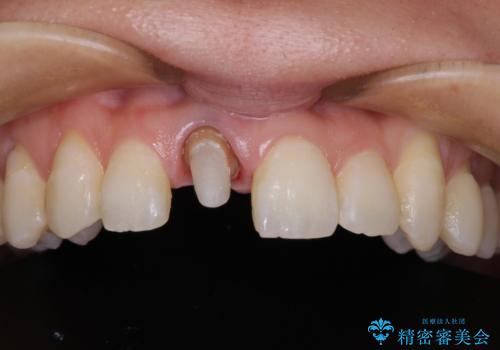

ファイバーコアにやり替えて、形を整え直して、

精度の高いシリコーンで型どりしました。